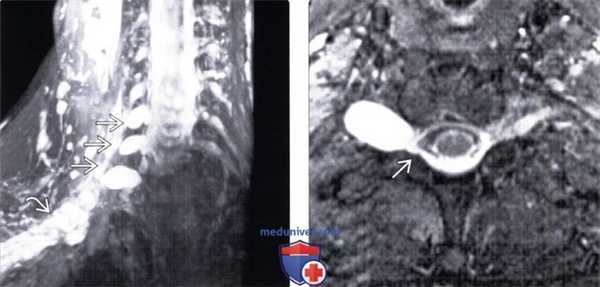

(Слева) FS Т2-ВИ фронтальная проекция: псевдоменингоцеле на уровне С5, С6 и С7. Корешки спинного мозга на этих уровнях отсутствуют, что связано с их разрывом и дистальной ретракцией. Стволы плечевого сплетения выглядят утолщенными и дряблыми.

(Справа) FS T2-BИ аксиальная проекция, этот же пациент: псевдоменингоцеле, распространяющееся через расширенное межпозвонковое отверстие С7-Т1. Корешок С8 был разорван ранее и здесь не виден.